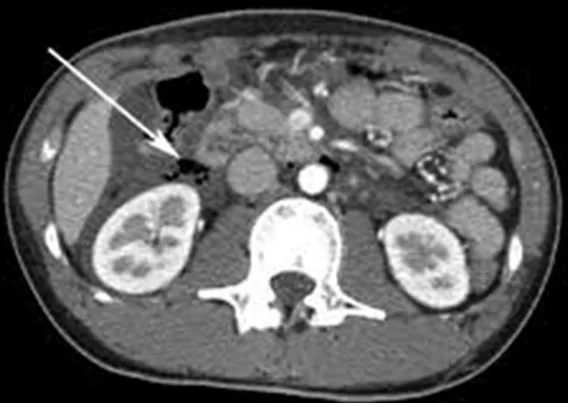

28세 여성이 자전거 사고 후 복통을 호소하며 응급실로 내원했다. 혈압 130/85 mmHg, 맥박 88회/분, 호흡수 15회/분, 체온 36.5℃로 측정되었다. 복부 진찰 결과 우측 상복부에 압통 및 경미한 반발압통이 관찰되었다. 복부 초음파 및 복부 CT 촬영 결과가 나왔다. 손상된 부위는 어디인가?

• 복부 X선, 복부 CT 상 신장 주위 retroperitoneal area에 저음영의 공기가 관찰되어 (perinephric air) 후복막 장기의 손상이 의심된다.